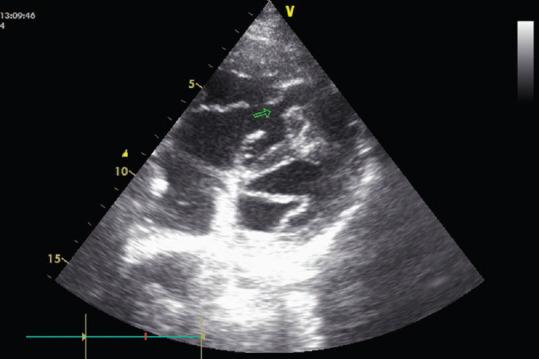

A double-chambered right ventricle (DCRV) is a rare congenital heart disease and an uncommon cause of congestive heart failure. An anomalous muscle band divides the right ventricle into two cavities: the proximal high-pressure chamber and the distal low-pressure chamber. Most cases are diagnosed and treated during childhood. Furthermore, there is a tendency for progression, if not treated early. Echocardiography is considered useful for the diagnosis of this ailment. Most of the patients have associated congenital anomalies, such as ventricular septal defect, pulmonary stenosis, and subaortic stenosis. Isolated DCRV is a rare entity. Hence, we report a case of an isolated DCRV in an adult patient.

双腔右心室(DCRV)是一种罕见的先天性心脏病,也是充血性心力衰竭的不常见病因。一条异常肌束将右心室分为两个腔:近端高压腔和远端低压腔。大多数病例在儿童期得到诊断和治疗。此外,如果不及早治疗,病情有进展的趋势。超声心动图被认为对诊断这种疾病有用。大多数患者伴有先天性异常,如室间隔缺损、肺动脉狭窄和主动脉瓣下狭窄。孤立性双腔右心室是一种罕见的情况。因此,我们报告一例成年患者的孤立性双腔右心室病例。